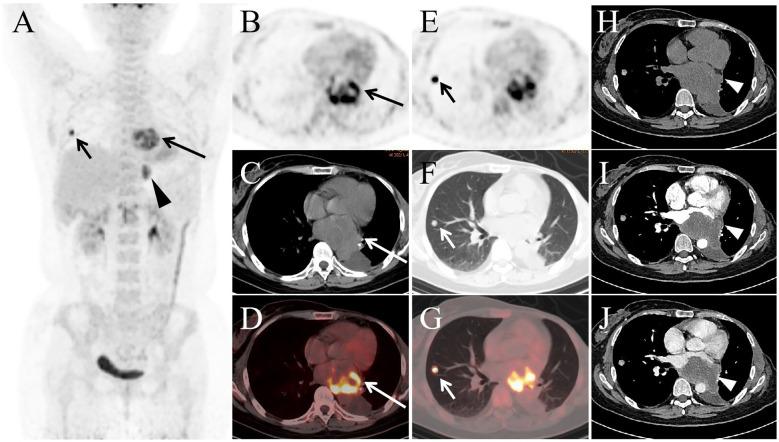

Metaplastic carcinoma of the breast is an extremely rare and highly aggressive malignancy associated with a poor prognosis. Breast spindle cell carcinoma is a subtype of metaplastic carcinoma. We present the case of a 48-year-old woman who was found to have a breast nodule during a routine examination two years ago. Pathological examination following surgical resection confirmed the diagnosis of breast spindle cell carcinoma. One year later, a follow-up CT scan detected a progressively enlarging mass in the left lower lobe of the lung, which was histologically confirmed as metastatic breast spindle cell carcinoma after surgical excision. Recently, the patient developed chest discomfort and severe left thigh pain, prompting anF-FDG PET/CT scan, which revealed metastases to the lung, heart, pleura, and femur. Subsequently, the patient's condition deteriorated rapidly within a short period. This report highlights the rare imaging findings of cardiac metastasis following surgery for breast spindle cell carcinoma, underscoring the highly aggressive nature of this tumor and the pivotal role ofF-FDG PET/CT in the post-operative monitoring of patients with breast spindle cell carcinoma.

乳腺化生性癌是一种极其罕见且侵袭性很强的恶性肿瘤,预后较差。乳腺梭形细胞癌是化生性癌的一种亚型。我们报告一例48岁女性病例,该患者两年前在常规检查中发现乳腺结节。手术切除后的病理检查确诊为乳腺梭形细胞癌。一年后,随访CT扫描发现左肺下叶有一逐渐增大的肿块,手术切除后组织学证实为转移性乳腺梭形细胞癌。最近,患者出现胸部不适和左大腿剧痛,促使进行F-FDG PET/CT扫描,结果显示肺、心脏、胸膜和股骨均有转移。随后,患者病情在短时间内迅速恶化。本报告强调了乳腺梭形细胞癌手术后心脏转移的罕见影像学表现,突出了该肿瘤的高度侵袭性以及F-FDG PET/CT在乳腺梭形细胞癌患者术后监测中的关键作用。